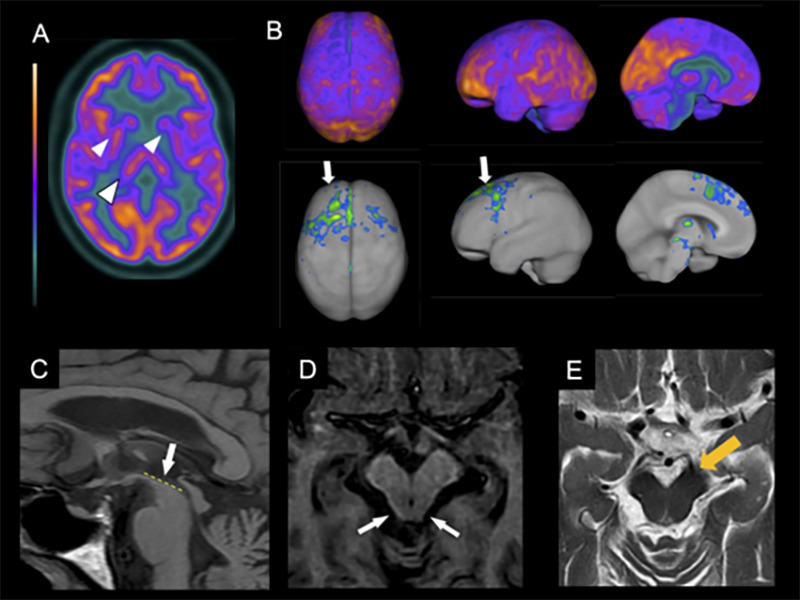

In PSP, the imaging hallmark is midbrain atrophy, which can be assessed through the visual identification of the “hummingbird sign”ref. B45 (specificity 99%, sensitivity 50%) on the sagittal plane, the “morning glory flower sign”ref. B46 (specificity 97%, sensitivity 37%) on the axial plane, and the superior cerebellar peduncle atrophy in the coronal plane (Figure 2)ref. B47 , ref. B48. More objective measures that can help diagnose PSP include the area, diameter, and volume of the midbrainref. B49, pons-midbrain area ratioref. B50, and the parkinsonism index MRPI (magnetic resonance parkinsonism index), calculated through the measurement of the ratios of the pons to midbrain area and middle cerebellar peduncle to superior cerebellar peduncle widthsref. B50. The latter is especially sensitive and specific for distinguishing PSP from PD, multiple system atrophy-parkinsonian type (MSA-P), and healthy controlsref. B51. Apparent diffusion coefficient (ADC) increased values in the putamen and superior cerebellar peduncle have good sensitivity and specificity in differentiating PSP-RS from PDref. B52. Also, diffusion tensor imaging (DTI) may show a degeneration pattern suggestive of PSP-RSref. B53.

CBD, in its turn, usually presents supratentorial patterns of atrophy, mainly asymmetrical patterns in the posterior frontal, superior parietal lobe, and basal ganglia (Figure 3). Cortical thinning and subcortical volume loss prominently involve the hemisphere contralateral to the more affected limb. Also, motor severity negatively correlates with the contralateral cortical thinning in the precentral and postcentral gyri and with volumes of putamenref. B59. Moreover, multimodal MRI studies search for CBS patterns of structural lesions that may suggest underlying pathology. A clinicopathologic study suggested that patterns of gray matter loss in CBS differ according to the underlying pathologyref. B60. Individuals with CBS and a postmortem diagnosis of CBD and PSP displayed similar focal atrophy at premotor and supplementary motor areas. In contrast, patients with underlying FTD-TDP43 and AD pathology had a more widespread pattern of gray matter loss at the frontotemporal lobe and temporoparietal regions, respectivellyref. B60.

The brain metabolic patterns obtained from FDG-PET assist in the early diagnoses of neurodegenerative diseases and is helpful to differentiate Parkinson’s disease from atypical parkinsonismref. B61 , ref. B62. FDG-PET in PSP-RS shows a characteristic pattern of hypometabolism in the midbrain, basal ganglia, thalamus, and frontal lobes, including prefrontal, anterior cingulate, premotor, and motor regionsref. B61 , ref. B63. A typical asymmetrical hypometabolism in CBD involves the frontal and parietal lobes, basal ganglia, and thalamus (Figure 2).